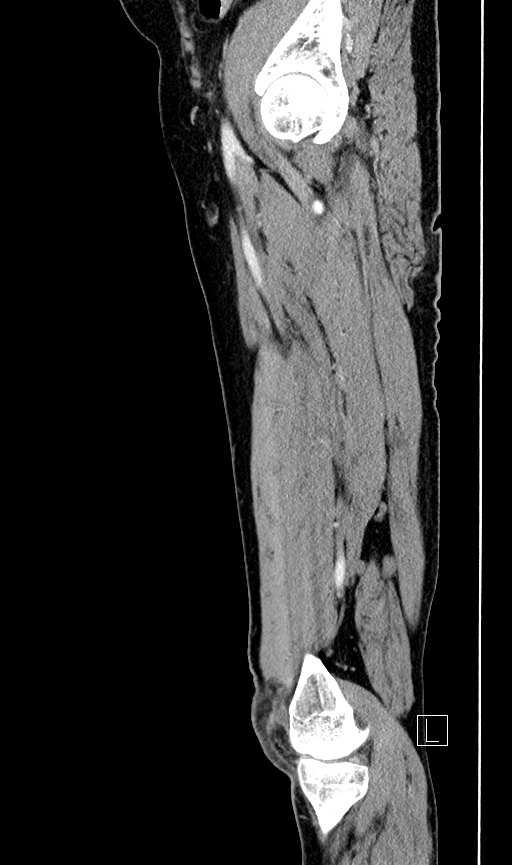

Sagittal Thigh 1

Index

Medial Femoral Condyle

Tibia

Vastus Medialis Muscle

Medial Head of Gastronemius Muscle

Semitendinosus Muscle

Semimembranosus Muscle